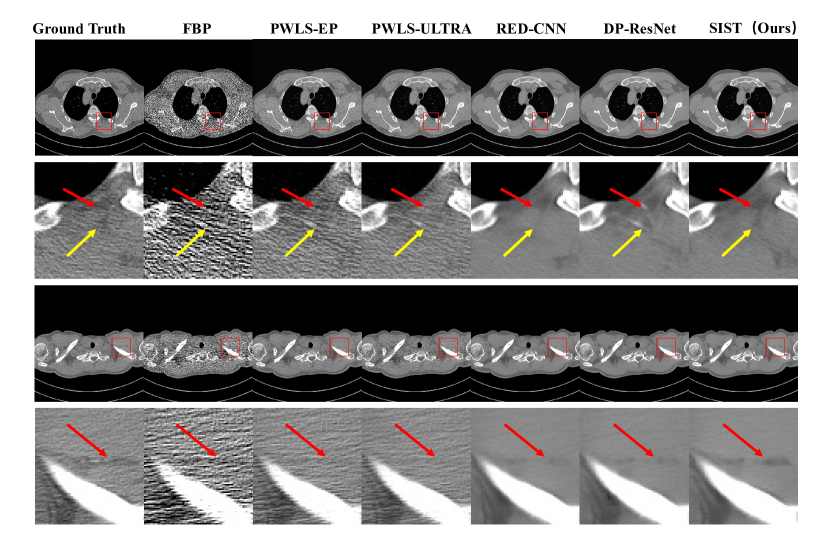

Figure 6: Visual results of 20% dose in Simulated Dataset. The first row is denoised images. The second row is zoomed regions in red boxes. All images displayed are from the same window of [-160, 240].

Refer to caption

Figure 7: Visual results of 10% dose in Simulated Dataset. The first row is denoised images. The second row is zoomed regions in red boxes. All images displayed are from the same window of [-160, 240].

4.3.2 Simulated Dataset

To further evaluate the performance of the proposed method on different dose levels, we generate the projection data and insert noise follow [39]. We evaluate the performance on three dose levels: 20%, 10%, and 5%. The quantitative results are shown in Tab.2. From the table, we can observe that our methods achieve the best results in all dose levels: 20%, 10%, and 5%. Same as the LDCT dataset, the deep learning methods show superior performance that iterative reconstruction methods. Moreover, our method still has great performance at the very low dose situation (5% dose), which even over the path the second method in 10% dose. Fig.6, Fig.7, and Fig.8 show the visual results for dose levels 20%, 10%, and 5%. From these visual results, we can observe that our method can preserve more details while denoising.